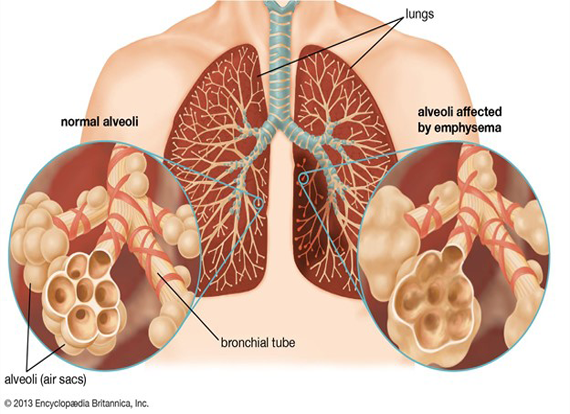

– Emphysema